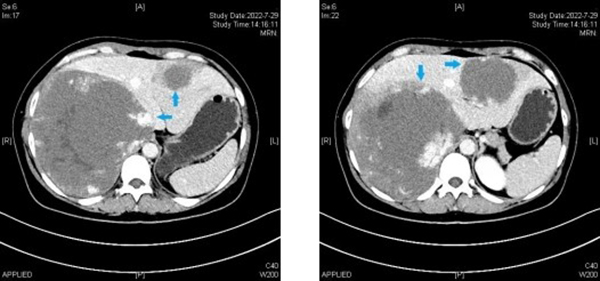

臨床上,病灶直徑10㎝以上就屬于巨大肝血管瘤。本例患者肝血管瘤共兩枚,分別位于肝左右葉,其中肝右葉瘤體直徑超過(guò)20cm,而肝左葉瘤體直徑也達(dá)到9cm,瘤體總體積甚至遠(yuǎn)超殘余肝臟體積。而右葉瘤體又發(fā)生于肝臟S7、8段,是腹腔鏡肝臟手術(shù)最困難的區(qū)域。由于瘤體巨大,壓迫膈肌,致膈肌上抬,同時(shí)擠壓人體最粗的血管下腔靜脈和腹主動(dòng)脈,使其受壓變形并移位。瘤體在肝內(nèi)則緊鄰菲薄的右肝及中肝靜脈,并且與入肝血流的門戶——第一肝門關(guān)系密切。術(shù)中一旦損傷上述血管,就會(huì)導(dǎo)致難以控制的大出血,氣體栓塞,肝功能衰竭等危及生命的并發(fā)癥。同時(shí)由于瘤體巨大,在手術(shù)切除瘤體過(guò)程中又要盡量保留正常肝臟組織的體積及功能。患者既往有兩次婦科手術(shù)史,腹腔粘連也是微創(chuàng)手術(shù)操作的攔路虎。但考慮到患者是年輕女性,對(duì)美觀及微創(chuàng)有著強(qiáng)烈的愿望。劉斌、魏鑫團(tuán)隊(duì)在進(jìn)行充分評(píng)估及術(shù)前準(zhǔn)備后仍決定為患者實(shí)施腹腔鏡手術(shù)。2022年8月2日,手術(shù)在馬萬(wàn)林麻醉團(tuán)隊(duì)低中心靜脈壓控制、自體血回輸?shù)谋U舷潞投规面玫茸o(hù)理團(tuán)隊(duì)的精準(zhǔn)配合下取得了圓滿成功;颊咝g(shù)后第一天即下床活動(dòng)進(jìn)并進(jìn)食流質(zhì)飲食,1周后拔除引流管出院。